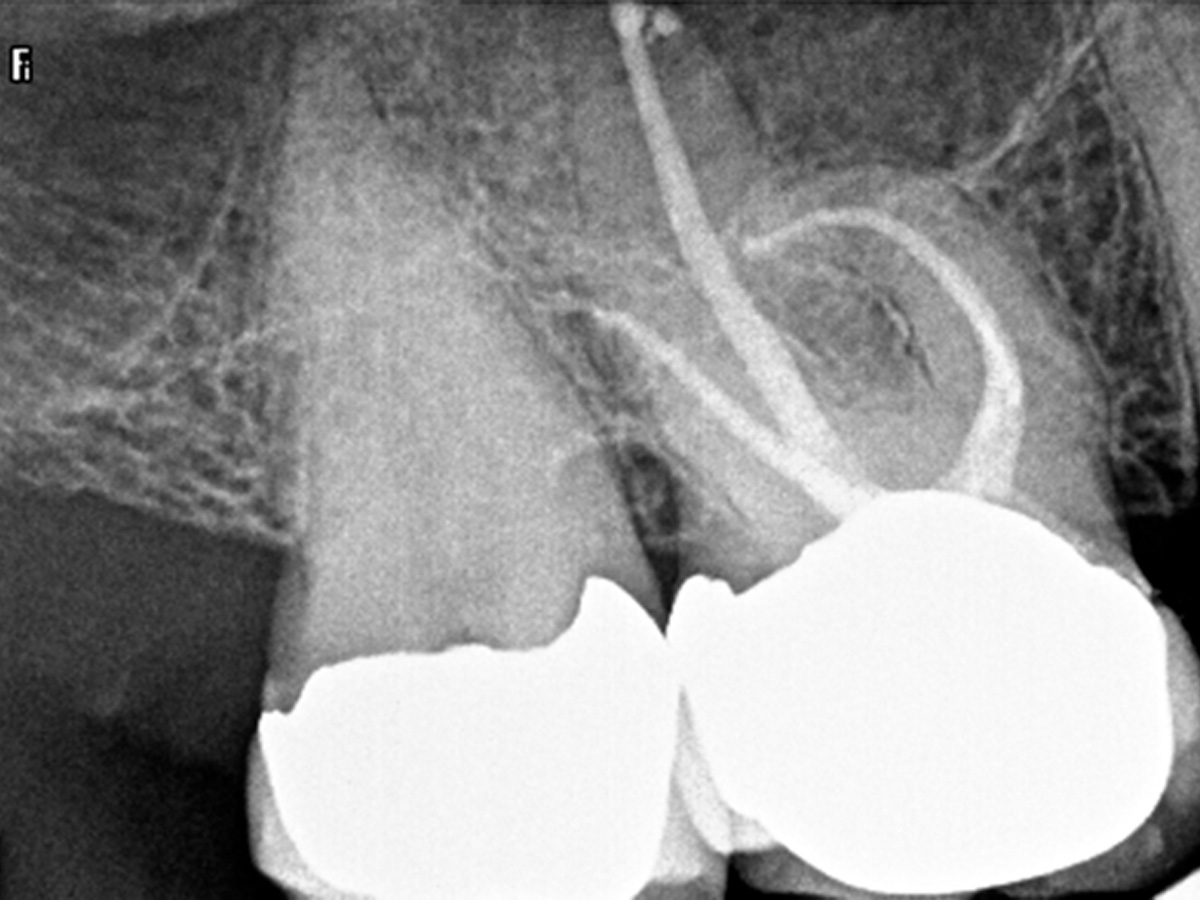

Abbildung 2

Nach der DVT-Untersuchung (Kodak 9000 3D, Auflösung 0,076 mm) bestätigte sich eine apikale Parodontitis an Zahn 16 palatinal. Eine Wurzelkanalbehandlung an Zahn 16 ist indiziert.